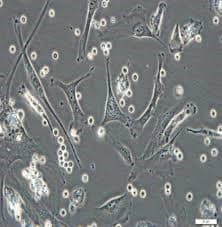

Sivas Cumhuriyet Üniversitesi Tıp Fakültesi öğrencilerinin hazırladığı “Hücre Kültürü Eğitim Programı” isimli projeye İKSAD International tarafından uluslararası destek verileceği açıklandı.

Dr. Öğr. Üyesi Mustafa Ergül ve Dr. Öğr. Üyesi Bilal Şahin’in katkıları, Dr. Öğr. Üyesi Ahmet Şevki Taşkıran’ın ise koordinatörlük görevini üstleneceği proje Said Yasin Şimşek ve Ahmet Turan İnce isimli Tıp Fakültesi öğrencileri tarafından hazırlandı. Tıp fakültesi öğrencilerinin genel anlamda bilimsel bir çerçevede bakış açısı geliştirmesinin amaçlandığı projenin Türkiye’de ilk defa gerçekleştirileceği belirtildi.

Proje kapsamında 6 farklı tarih belirlenecek ve toplamda 60 farklı Tıp Fakültesi öğrencisine hücre kültürü eğitimi verilecek. Ayrıca verilecek eğitimlerin görüntüleri kayıt altına alınarak daha sonrasında faydalanmak isteyen öğrencilerin erişimine açık olacak.